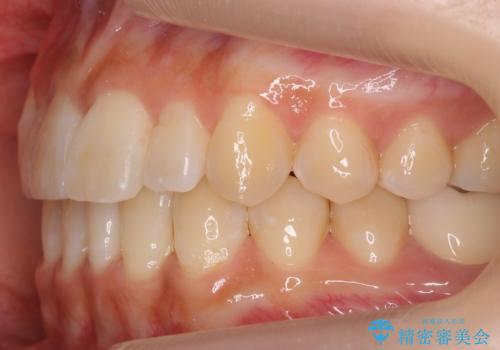

八重歯 インビザラインで抜歯矯正 ただし1本のみの抜歯で済みます

- 八重歯を治したいと来院。

古典的な治し方ですと上下左右4本抜歯してワイヤー矯正です。

今回は口元も出ていないうえに、右上のみの八重歯のため奥歯を後ろに下げて治療しました。

ただし、下の前歯は入りきらない為1本のみ抜歯しています。

右上の犬歯をおろしてくるのに、顎間ゴムを使用しています。